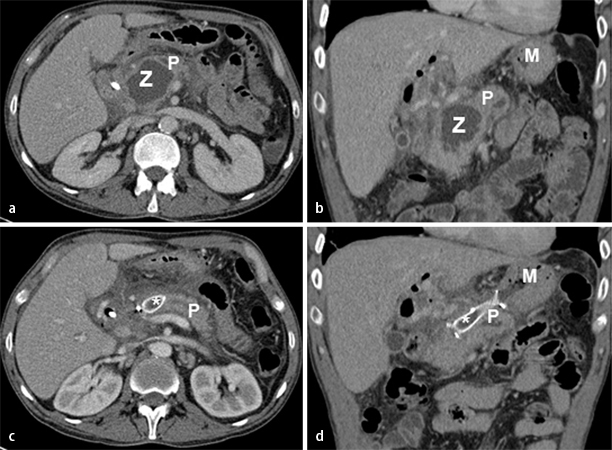

Einen herausragenden Stellenwert

Einen herausragenden Stellenwert hat die ERC/ERCP im Therapiealgorithmus der akuten Pankreatitis biliärer Genese

hat die endoskopisch retrograde Cholangiographie (ERC)/ERCP (+Pankreatographie) im Therapiealgorithmus der akuten Pankreatitis biliärer Genese (deutlicher Anstieg der Cholostaseparameter). Indikationen zur sofortigen ERC (innerhalb von 24 h) ggf. mit Steinextraktion und Stent-Implantation bestehen bei Cholangitis oder Cholangiosepsis [1]. Bei den übrigen Fällen einer biliären Pankreatitis mit Konkrementnachweis und Gallenaufstau sollte eine ERC/ERCP innerhalb von 72 h stattfinden. Bei unklaren Situationen kann die Endosonographie wertvolle Dienste leisten. Ein weiteres Einsatzgebiet der Endoskopie besteht in der Therapie von Pseudozysten, die transpapillär oder transgastral drainiert werden können (Abb. 2). Ebenfalls ein innovatives Verfahren stellt die endoskopische transgastrische oder transduodenale Nekrosektomie zur Behandlung infizierter Nekrosen oder Abszesse dar [20].

Chirurgische Therapie

Neben der elektiven Cholezystektomie bei biliärer Pankreatitis mit Nachweis von Cholezystolithiasis zur Senkung des Rezidivrisikos ist die chirurgische Nekrosektomie (Abb. 3) eine mögliche Therapieoption bei komplizierten Verlaufsformen. Jedoch hat sich vor dem Hintergrund potenter Breitbandantibiotika und immer innovativerer interventioneller Verfahren auch in der Therapie superinfizierter Nekrosen ein Paradigmenwechsel vollzogen: Seit rund 20 Jahren verdichtet sich die Studienlage, die mit dem alten Dogma bricht, dass infizierte Nekroseareale per se eine Operationsindikation darstellen. So untersuchte die hochkarätig publizierte niederländische Studie Minimally Invasive Step-up Approach versus Maximal Necrosectomy in Patients with Acute Necrotizing Pancreatitis (PANTER; [21]) aus 2010 die „Step-up“-Strategie , also eine schrittweise Eskalation mit breiter Antibiokagabe, perkutaner Drainage, ggf. gefolgt von minimal-invasiver retroperitonealer Nekrosektomie, im Vergleich zu primär offener chirurgischer Nekrosektomie bei 88 Patienten mit schwerer nekrotisierender Pankreatitis. Bezüglich des primären Endpunkts (Letalität oder schwere Komplikationen, Organversagen und Spätkomplikationen stellte sich in dieser Studie der „Step-up“-Ansatz als überlegen heraus [21]. Die gleiche Arbeitsgruppe konnte in einer Nachfolgestudie 2011 belegen, dass